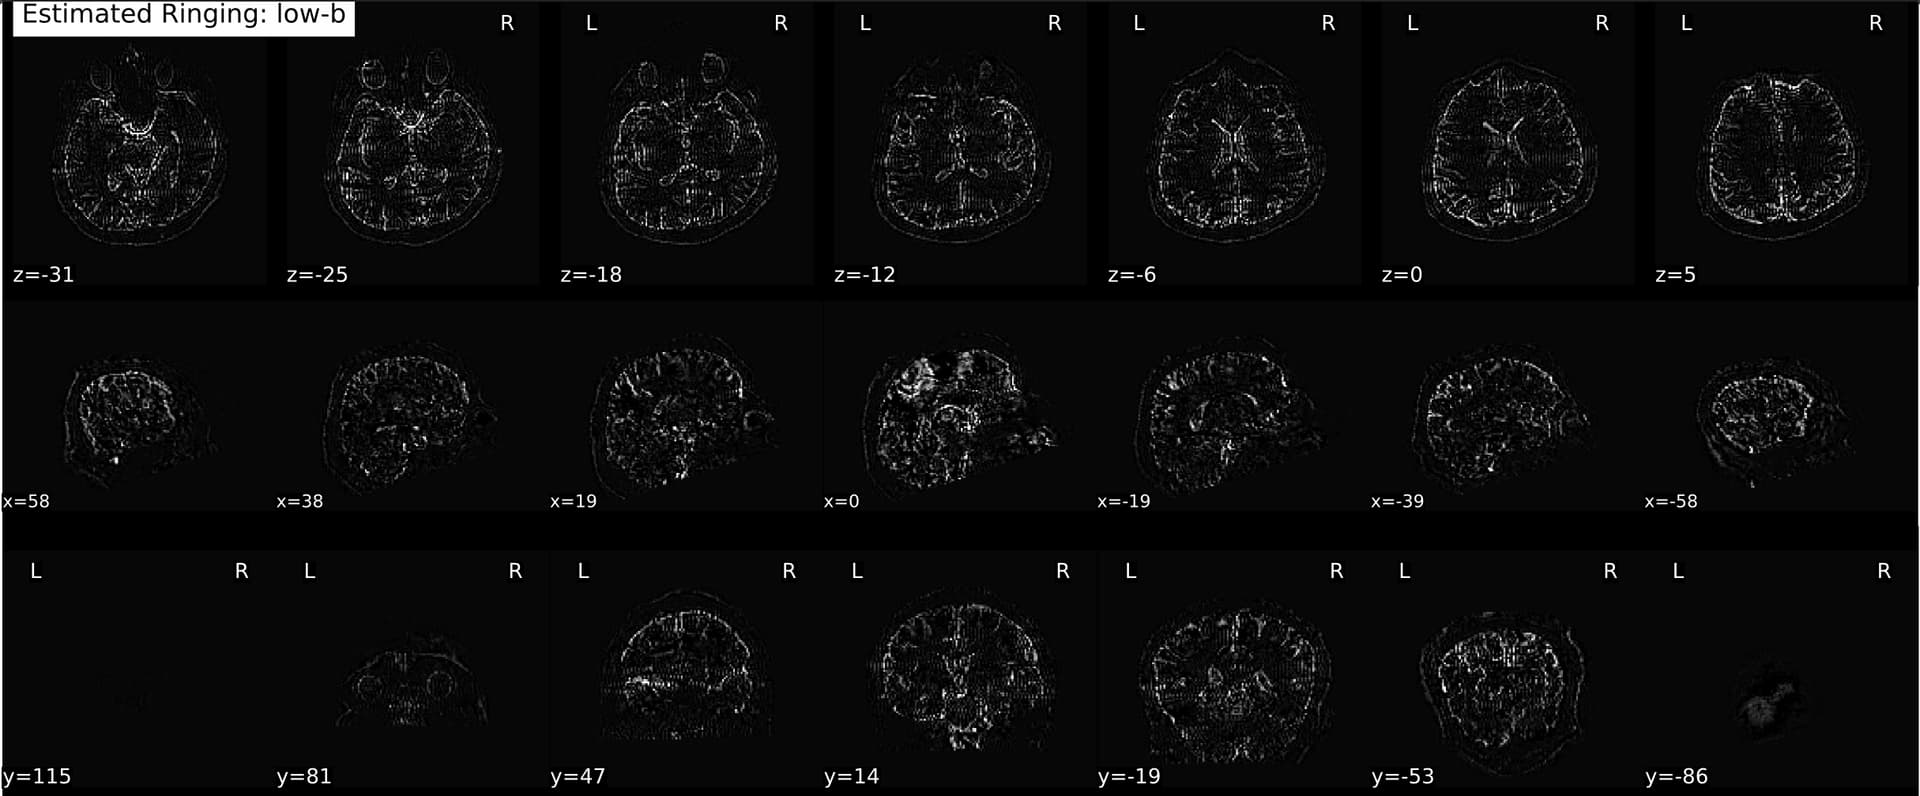

Waiting on the full pipeline to run so I can compare the final outputs, but for now, definitely looks like it’s an RPG issue.

Here’s an example cs-DSI collected at UCSB:

A Q4 also at UCSB:

And the same sequence but collected at another site:

Much more like what I’d expect! I suppose the (extremely loaded) question at this point is just whether mrdegibbs is appropriate to use for PF DSI data. I know it was designed for full-Fourier acquisitions, but from what I’m reading it’s probably ok? Also have been working with neuroimaging data long enough to know that there is rarely a straightforward answer as to what the ‘best’ preprocessing methods are haha, but I assume some Gibbs unringing is probably preferable to none, and mrdegibbs at least seems to provide something more sensible.